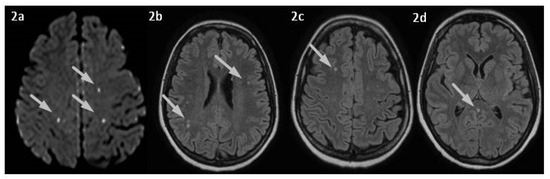

2. Case Presentation